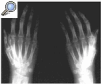

Fig. 1. Osteopenia detectada en la radiografía de las manos.